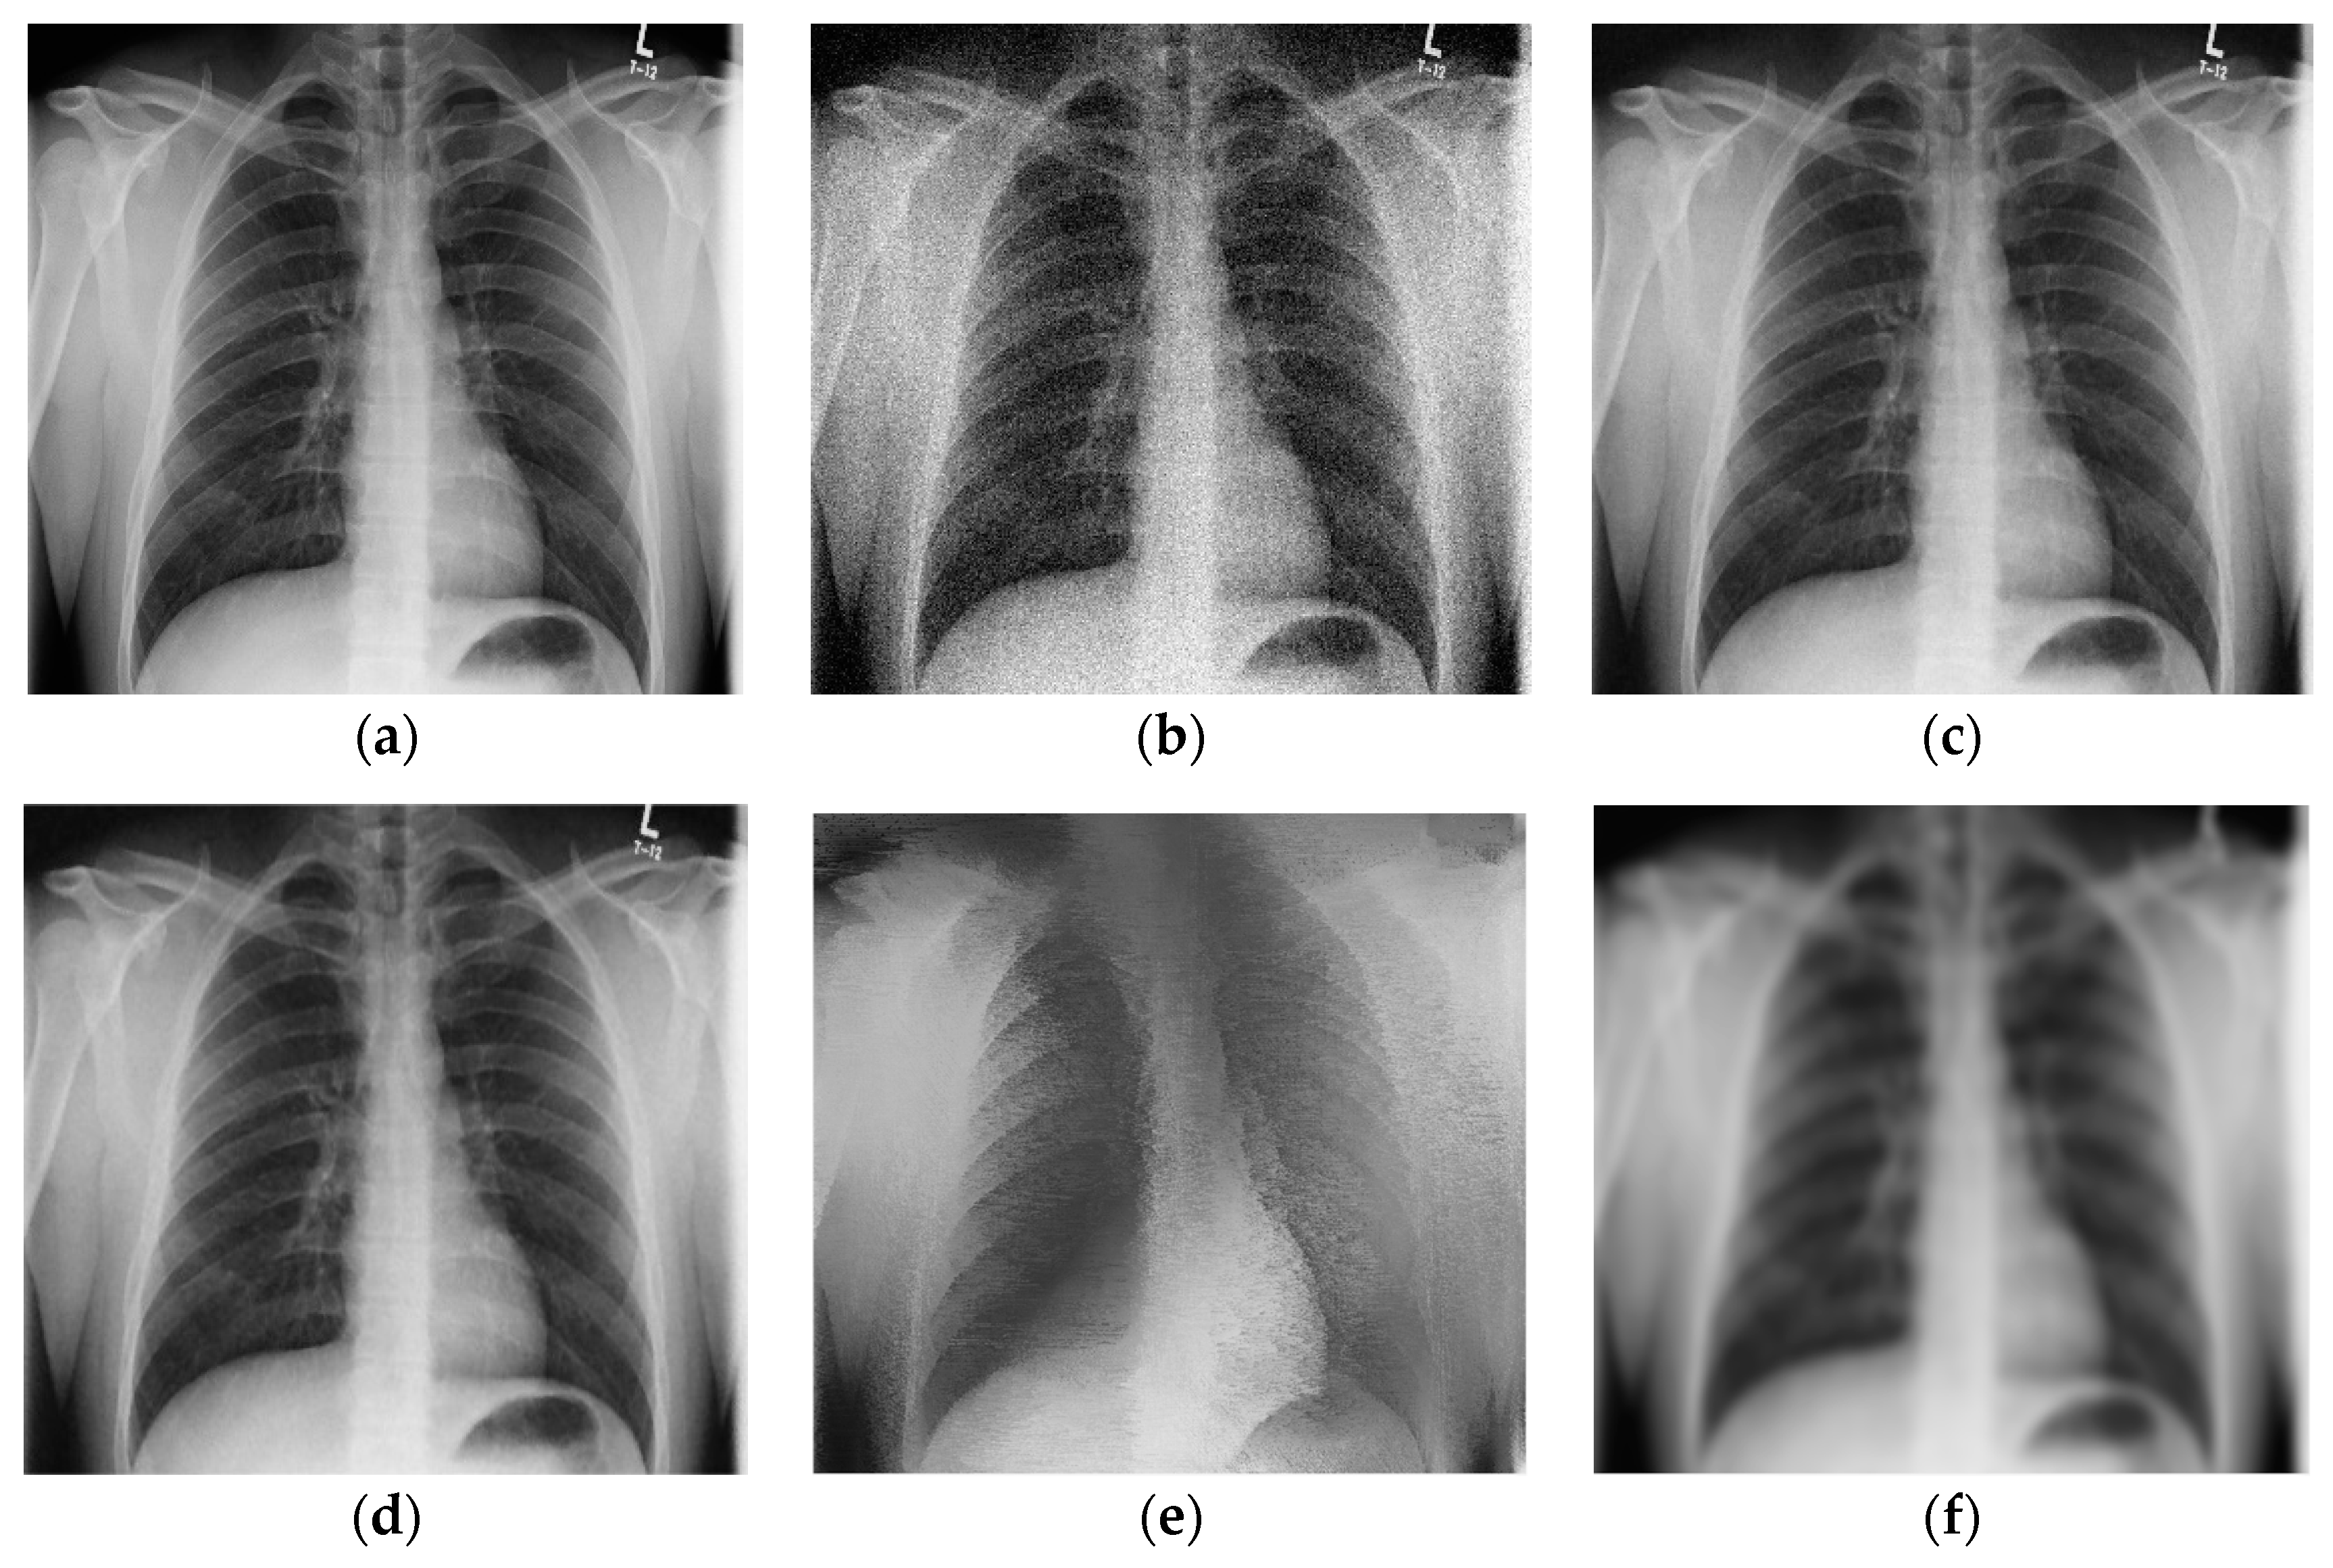

Denoised ankle X-ray images (with resolution 600 × 682) are given in Figure 5. Figure 5a,b show noise-free and noisy images, respectively. Figure 5c–e shows the denoised images obtained using the 2D LPA-RICI method with quadrilateral, octagonal and hexadecagonal regions, respectively.

Figure 5.

Ankle X-ray scan. (a) Original noise-free image; (b) Noisy image (AWGN with σ = 25); (c) Image denoised using the 2D LPA-RICI method (quadrilateral region, Г = 1.8, Rc = 0.8); (d) Image denoised using the 2D LPA-RICI method (octagonal region, Г = 1.8, Rc = 0.8); (e) Image denoised using the 2D LPA-RICI method (hexadecagonal region, Г = 1.8, Rc = 0.8); (f) Image denoised using Gaussian smoothing filters; (g) Image denoised using total variation denoising.

Table 5 gives the PSNRs of the denoised ankle X-ray images. The proposed 2D LPA-RICI method, as it was the case for other two test images, outperformed fixed size 2D filtering in all cases. Furthermore, it also increased the denoised image PSNR when compared to the Gaussian smoothing filters and the total variation denoising (when quadrilateral or octagonal regions were used).

As it can be seen from Table 6, ankle X-ray scan denoised by the 2D LPA-RICI method with quadrilateral regions resulted in an increased PSNR (compared to the noisy image) by up to 8.09 dB, by up to 7.46 dB with octagonal regions and by up to 3.93 dB with hexadecagonal regions. Once again, the proposed 2D LPA-RICI method was shown to significantly outperform the fixed size 2D median filtering. In addition, it also outperformed Gaussian smoothing filter method for all tested regions (including hexadecagonal regions, which was not the case in the previous examples) by up to 5.46 dB. Furthermore, it increased the denoised PSNR when compared to the total variation denoising method by up to 2.80 dB (when quadrilateral and octagonal regions were used).